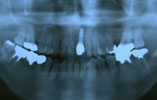

CASE8

上顎、下顎に多数の歯が抜けている場合 審美的・機能的に回復

インプラント埋入前

インプラント埋入後

インプラントに

セラミッククラウンを装着

術前

術後

上顎、下顎とも多数欠損により、長い間上手く噛めませんでした。CT撮影後、上顎に4本、下顎に5本のインプラントを埋入し、

固定式のブリッジを装着することにより、審美的、機能的回復をいたしました。